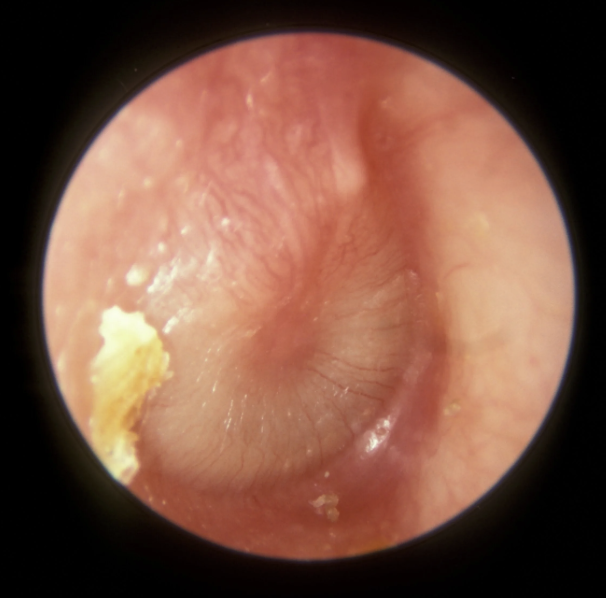

Otitis externa

Infection of the outer ear (ear canal)

<p>Infection of the outer ear (ear canal)</p>